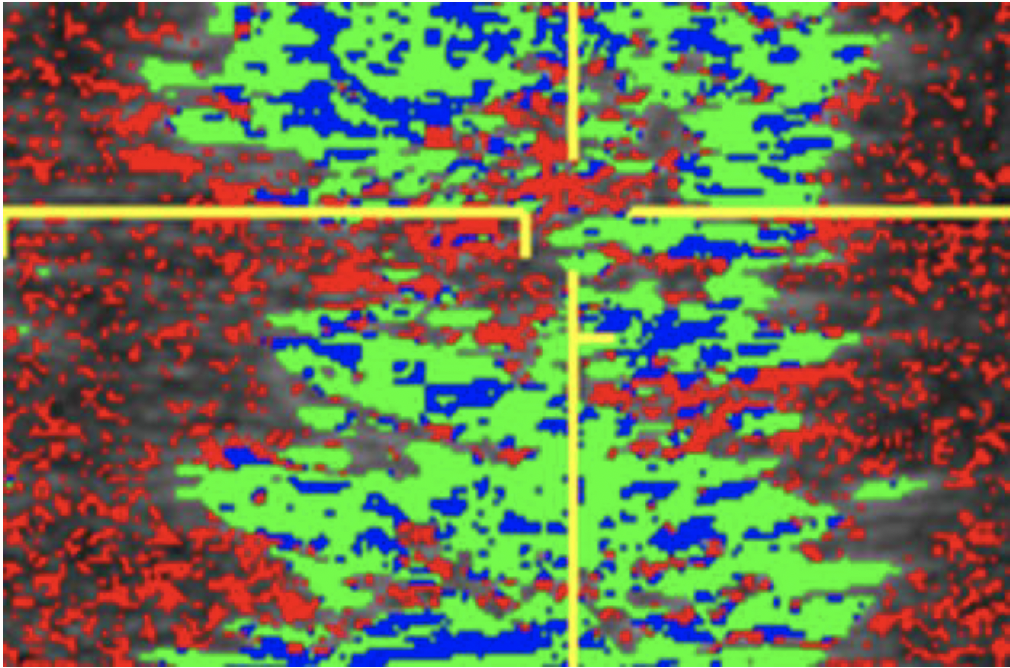

Courtesy, Hans T.M. van Schie, DVM, PhD

Courtesy, Hans T.M. van Schie, DVM, PhD

Recently, in both human and veterinary medicine, the technique of ultrasound tissue characterization, also known as UTC, has been utilized to fill in the gaps created by traditional ultrasound. In this technique, a standard ultrasound probe is placed in a motorized tracking device. This device is placed on the horse’s skin over the tendons. The probe is automatically moved along a track that allows it to uniformly scan a length of leg. A 12-centimeter length is scanned in 45 seconds. Images are captured every 0.2 millimeters. The over 600 images and information produced are digitally manipulated to generate a 3D tendon representation.

This precise “spatial stacking” of images provides a much more detailed and accurate representation of the tendon and various areas along the scanned length. This is proving extremely helpful, as most tendon injuries are found to involve varying lengths and depths along the limb with pockets of better fibers intermixed with areas of more serious damage. This subtlety is missed with a standard ultrasound but is better defined with 3D tissue characterization.

The ability to, in a standardized and repeatable way, rescan the exact same area and create another 3D representation in two weeks or so allows the clinician to monitor specific areas within the tendon and to stay focused on those individual areas and the repair process. This more directed monitoring opens the door to more correct utilization of other treatment options such as specific injections of regenerative products into certain nonhealing or slowly responding areas, even when closely surrounding tissue is healing well. It will allow the use of shockwave therapy, pulsed electromagnetic wave therapy or other modalities in other directed areas when necessary and better incorporation of physical therapy at appropriate times.